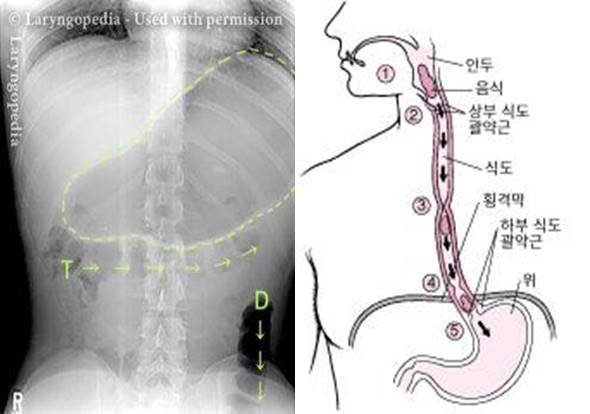

역행성 윤상인두근 기능장애는 상부 식도 괄약근이 수축되어 트림이 배출되지 못하는 질환을 말한다. 보통 음식을 삼키면 상부 식도 괄약근이 열려 음식이 식도에 유입된다. 이때 괄약근이 수축하면서 음식이 아래로 내려간다. 이후 괄약근이 이완돼 트림이 방출되는 ‘역행 작용’을 거치는데, 괄약근이 제때 이완하지 못해 역행 작용이 어려운 질환이 역행성 윤상인두근 기능장애다. 이 질환은 미국 바스티안 음성 연구소(Bastian Voice Institute) 소장 로버트 바스티안이 트림을 못하는 환자들을 조사하면서 2019년에 처음 명명했다. 발병 원인은 아직 밝혀지지 않았다. 다만 이후 전세계적으로 이 질병에 대한 인식이 확산되면서 같은 질환을 앓는 사람들이 커뮤니티를 형성하고, 관련 연구가 활발히 진행되고 있다.